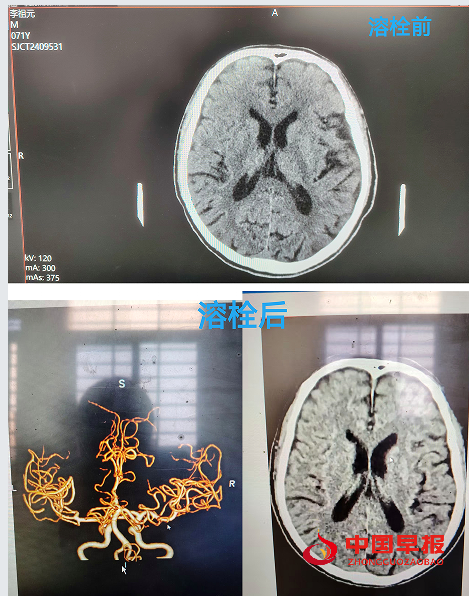

中国早报湖北沙洋讯(记者 王光兴 通讯员 构月华 毛草婷)3月6日,湖北荆门市沙洋县沈集镇中心卫生院成功完成首例急性脑卒中溶栓治疗,这是该院在医疗技术领域的重大突破,也为区域内患者带来了新希望。

当天下午13时许,沈集镇雨林村的李爷爷在家中突发口角歪斜、言语含糊、左侧肢体无力,家属发现后,迅速将其送至沈集镇中心卫生院急诊室内,争分夺秒的战斗悄然打响,医护人员迅速启动“脑卒中绿色通道”。经过一系列检查,确诊患者为急性脑卒中且处于溶栓时间窗内,时间就是生命,医护人员立即对患者实施静脉溶栓治疗,治疗过程中,医护人员紧密配合,紧盯老人各项生命体征的细微变化,确保每一个环节都精准无误。溶栓后,患者生命体征稳定。为进一步巩固治疗效果,老人被转送至上级医院进行后续治疗,1小时后,经上级专家反馈患者状态明显好转,溶栓效果良好。

这次急性脑卒中溶栓治疗的成功,也是该院卒中防治站建设达标的强有力证明。未来,沈集镇中心卫生院将始终秉承“以患者为中心”的服务理念,不断提升医疗技术水平和服务质量,为广大群众的生命健康保驾护航,在守护健康的道路上,永不止步,再创佳绩。